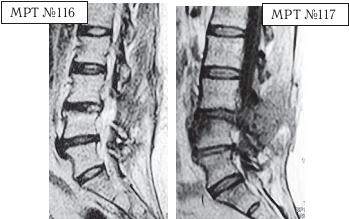

На МРТ № 116 (в режиме Т2-ВИ) и МРТ № 117 (в режиме Т1-ВИ) той же пациентки наблюдается состояние через три месяца после хирургического вмешательства.

На МРТ № 117 в режиме Т1-ВИ отчётливо видно, что был прооперирован межпозвонковый диск в сегменте LIII—LIV вместо диска в сегменте LIV-LV В передней части тела позвонка LIV наблюдается очаг воспаления, реактивный асептический дисцит (частая и можно сказать естественная реакция тканей на операцию, вследствие развития аутоиммунных реакций).

Нейрохирург, ознакомившись с результатами обследования МРТ и увидев, что произошла ошибка (был прооперирован не тот межпозвонковый диск), настоял на проведении ещё одной операции. Естественно, пациентка не хотела идти на вторую операцию на позвоночнике, так как уже была напугана результатами первой операции. Однако лекарства не помогали, а боли, по её словам, «просто сводили с ума». В общем, она согласилась на повторную операцию.